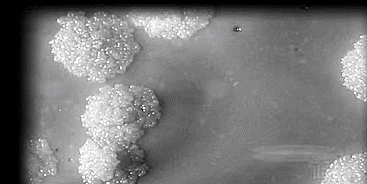

它的病原体叫结核菌

肺结核与新冠肺炎同样属于呼吸道传染病,存在着很多共同之处,比如都有咳嗽、发热、肺部感染症状,传播方式以呼吸道飞沫传播为主,病人都需要戴上口罩。